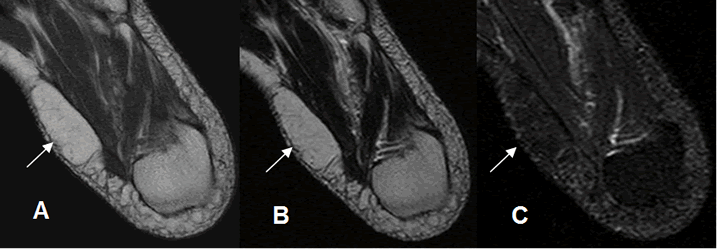

Fig 161. Lipoma.

A: RM axial en T1, B: RM axial en T2 y C: RM axial en STIR. Lesión ovalada y encapsulada en la parte interna del pie, hiperintensa en T1 y T2 y que suprime en STIR, que corresponde a lipoma.